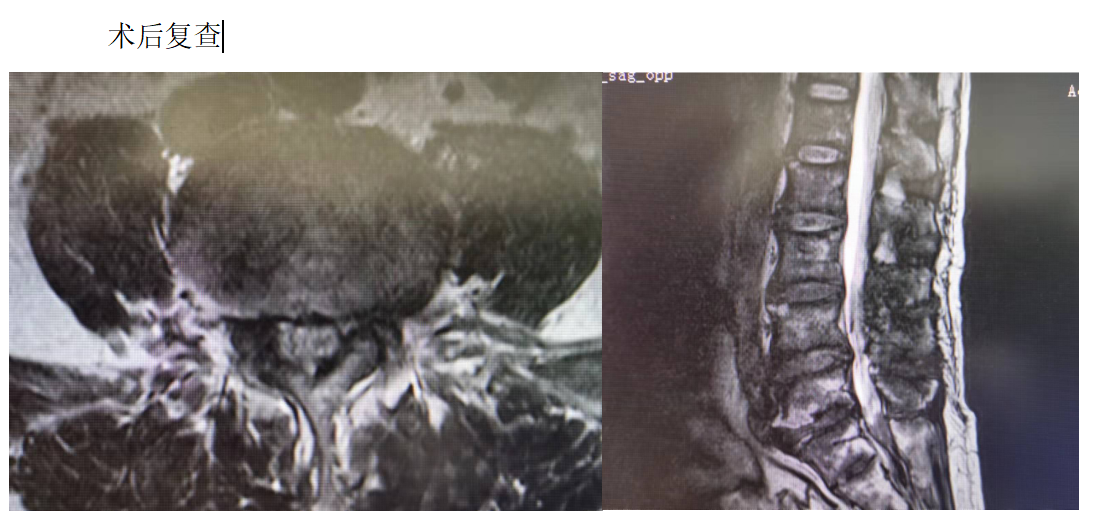

主诉:腰部疼痛3年,加重伴双下肢疼痛麻木1年

现病史:3年前出现腰部疼痛、酸困,无下肢疼痛麻木不适,弯腰活动受限,行走及站立时疼痛加重,平卧休息稍减轻,未治疗,上述症状持续加重,近1年来又出现双下肢疼痛麻木,以左侧为著,步行困难,步行能力约100米,为求诊治,现来我院,遂以“腰椎管狭窄症”为诊断收住我科。发病以来,饮食正常,睡眠一般,体力正常,大小便正常。